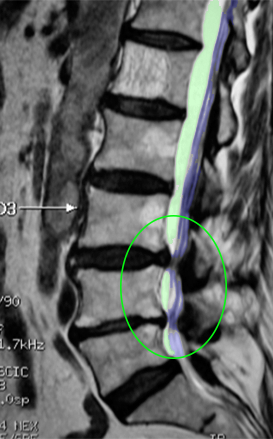

Η στένωση του οσφυϊκού σπονδυλικού σωλήνα είναι μια από τις πιο συχνές παθήσεις της οσφυϊκής μοίρας της σπονδυλικής στήλης. Ορίζεται ως η μείωση του εμβαδού του σπονδυλικού σωλήνα, οποιασδήποτε αιτιολογίας, με αποτέλεσμα την πίεση στα νεύρα που νευρώνουν τα κάτω άκρα προκαλώντας άλγος σε αυτά και εύκολη κόπωση στη βάδιση με συχνές στάσεις για ξεκούραση, μια κατάσταση που ονομάζεται νευρογενής διαλείπουσα χωλότητα. Η θεραπεία εξαρτάται από τον βαθμό και την ένταση των συμπτωμάτων και είναι συχνά χειρουργική. |

Επίπτωση και αιτίες Περίπου 10% του πληθυσμού πάσχει από διαφόρους βαθμούς στένωσης του οσφυϊκού σπονδυλικού σωλήνα με το μεγαλύτερο μέρος του ποσοστού αυτού να βρίσκεται στις ηλικίες άνω των 50. Οι αιτίες συμπεριλαμβάνουν την κήλη του οσφυϊκού μεσοσπονδυλίου δίσκου σε συνδυασμό συνήθως με εκφυλιστική αιτιολογίας υπερτροφία των μικρών αρθρώσεων της σπονδυλικής στήλης και του ωχρού συνδέσμου η οποία είναι και η συχνότερη αιτία. Άλλες αιτίες είναι η οσφυϊκή σπονδυλολίσθηση, οι όγκοι και τα κατάγματα της οσφυϊκής μοίρας της σπονδυλικής στήλης. Σε αυτή την ενότητα θα περιγραφεί κυρίως η εκφυλιστικής αιτιολογίας στένωση του οσφυϊκού σπονδυλικού σωλήνα η οποία είναι και η πιο κοινή. |

Φυσιολογικός ευρύς σπονδυλικός σωλήνας αριστερά (πράσινο) με άφθονο χώρο γύρω από τα νεύρα (βέλος). Στενός σπονδυλικός σωλήνας δεξιά με συμπίεση των νεύρων. |